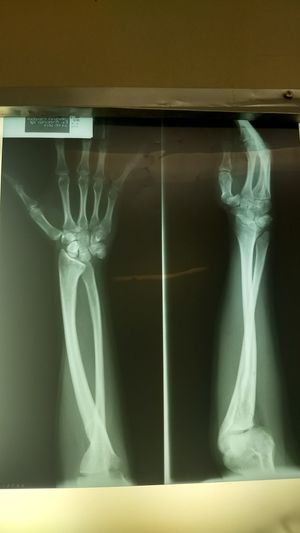

Deformidad de Madelung